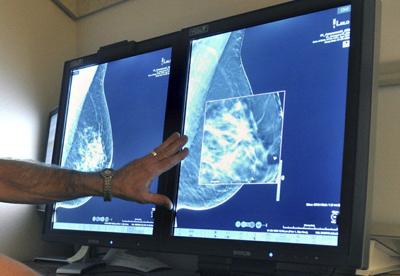

FILE - This July 31, 2012, file photo shows a mammogram, a test to detect cancer. (Torin Halsey/Times Record News via AP, File)

(FOX NEWS) -- A new Google artificial intelligence model appears capable of more accurately spotting breast cancer in mammograms than radiologists.